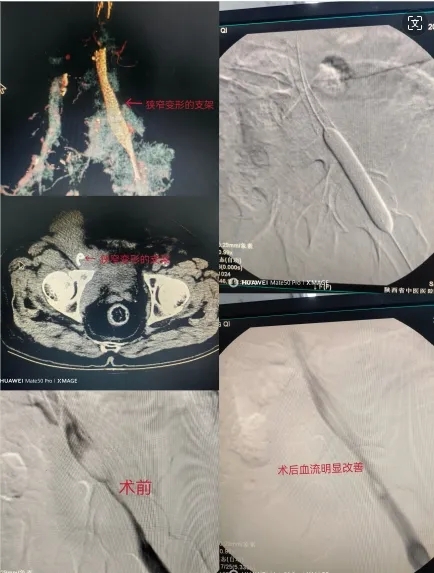

患者冯某某,男,71岁,右下肢肿胀半年余,患者半年前因盆腔肿瘤致右髂静脉狭窄及右下肢深静脉血栓形成,后于我科行下腔静脉滤器置入术、下肢深静脉血栓抽吸术及髂静脉支架植入术,术后规律抗凝治疗,患者右下肢水肿逐渐消退。嘱患者需针对盆腔肿瘤积极诊治,否则有支架再狭窄风险。但患者拒绝后续治疗。近一月患者再次出现右下肢重度水肿,入院行盆腔CT及下肢CTV显示盆腔肿瘤较前明显增大,髂静脉支架重度狭窄。

周筱燕副主任医师医疗团队经过讨论认为:1、患者系肿瘤压迫导致髂静脉支架再狭窄,下肢CTV显示髂静脉支架重度狭窄并严重变形,手术再次开通难度大风险高。术前设计严密的手术方案,并设计备用方案以应对术中出现的各种意外状况。2.此次手术再次开通血管能否达到预期效果?支架的选择起到至关重要作用。以前没有髂静脉专用支架,患者植入的是常规血管支架,此类支架支撑力不强,故在肿瘤压迫下发生再狭窄。现我省有针对髂静脉狭窄的髂静脉专用支架,最终选定了支撑力更强的国产Penguin支架。因此款支架在陕西省为第一例使用,院方急患者之所急积极联系办理手续,手术顺利开展。在B超室徐华主任超声引导下,周筱燕副主任医师进行腘静脉穿刺置管,遂后于导管室造影见患者右侧髂静脉狭窄超过90%,周筱燕副主任医师、邓有峰主任默契配合-------造影、球囊扩张、支架植入一气呵成。

经过1个多小时的努力手术顺利完成。术后造影显示髂静脉开通达到预期。术后第二天患者皮肤紧绷感明显改善,大腿周径较术前减少了4cm。